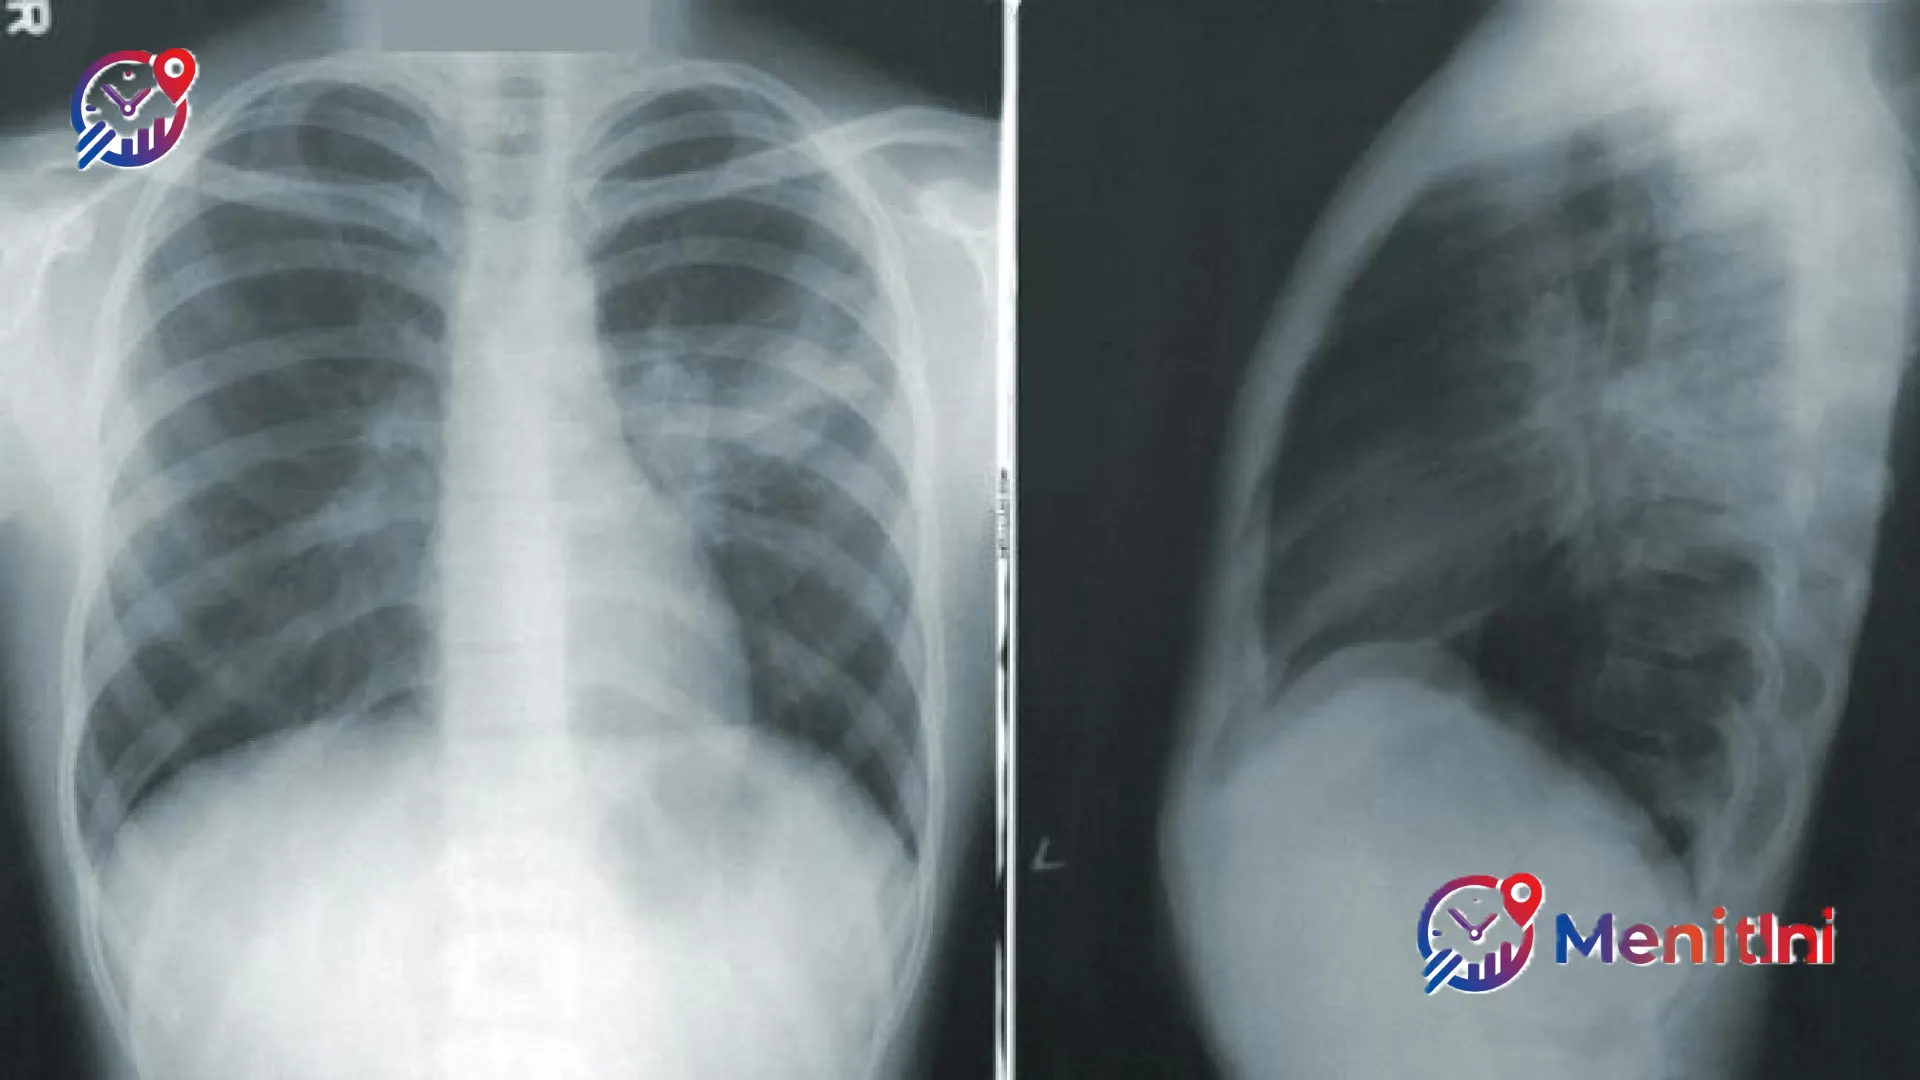

MenitIni — Realitas pahit membayangi dunia kesehatan Indonesia di mana penyakit Tuberkulosis (TBC) masih menjadi momok mematikan yang mengintai secara sunyi. Data terbaru menunjukkan angka yang menggetarkan: setiap empat menit, satu nyawa melayang akibat penyakit ini, sementara setiap menitnya, dua orang dinyatakan terinfeksi kuman yang menyerang paru-paru tersebut.

Kondisi ini bukan sekadar statistik, melainkan alarm keras bagi percepatan eliminasi TBC di tanah air. Wakil Menteri Kesehatan, dr. Benjamin Paulus Octavianus, mengungkapkan bahwa Indonesia mencatat beban kasus yang luar biasa besar, yakni melampaui satu juta kasus setiap tahunnya. Angka ini menempatkan Indonesia dalam daftar negara dengan beban TBC tertinggi di kancah global.

Program deteksi dini masif dianggap sebagai kunci utama untuk memutus rantai penularan. Dengan menemukan kasus lebih cepat, peluang pasien untuk sembuh total meningkat drastis, sekaligus menekan angka fatalitas. Wamenkes Benny menekankan bahwa tidak ada waktu untuk menunda tindakan, karena setiap detik keterlambatan berarti nyawa yang terancam.